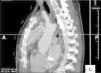

Ecocardiogramas transtorácicos seriados mantiveram‐se sobreponíveis pelo que foi realizada tomografia computorizada (TC) torácica que revelou pseudoaneurisma (4,5x4,5x8cm) face anterior da aorta ascendente, provavelmente com origem no local de canulação prévia (Figura 2).